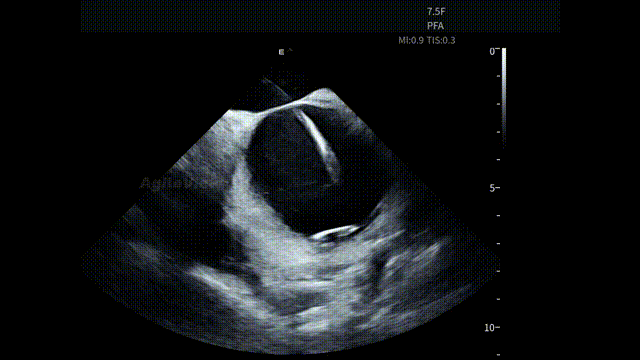

手术开始后,AgileView™ ICE 导管作为术中影像辅助工具,经股静脉穿刺进入心房。考虑到本台手术将搭配PulseSelect™消融导管使用,助手将ICE主机调整至“PFA预设模式”,便于后续更直观的判断导管贴靠情况。通过 HomeView 视角,术者首先了解了患者心腔整体结构,为操作提供统一的影像参考。

HomeView

随后,ICE对左心房、左心耳及心包区域进行系统性扫查。术前重点评估左心耳内是否存在血栓形成,并同步观察心包情况,确保在消融前,关键风险已被充分排查,为保证手术安全提供直观依据。

术前心包